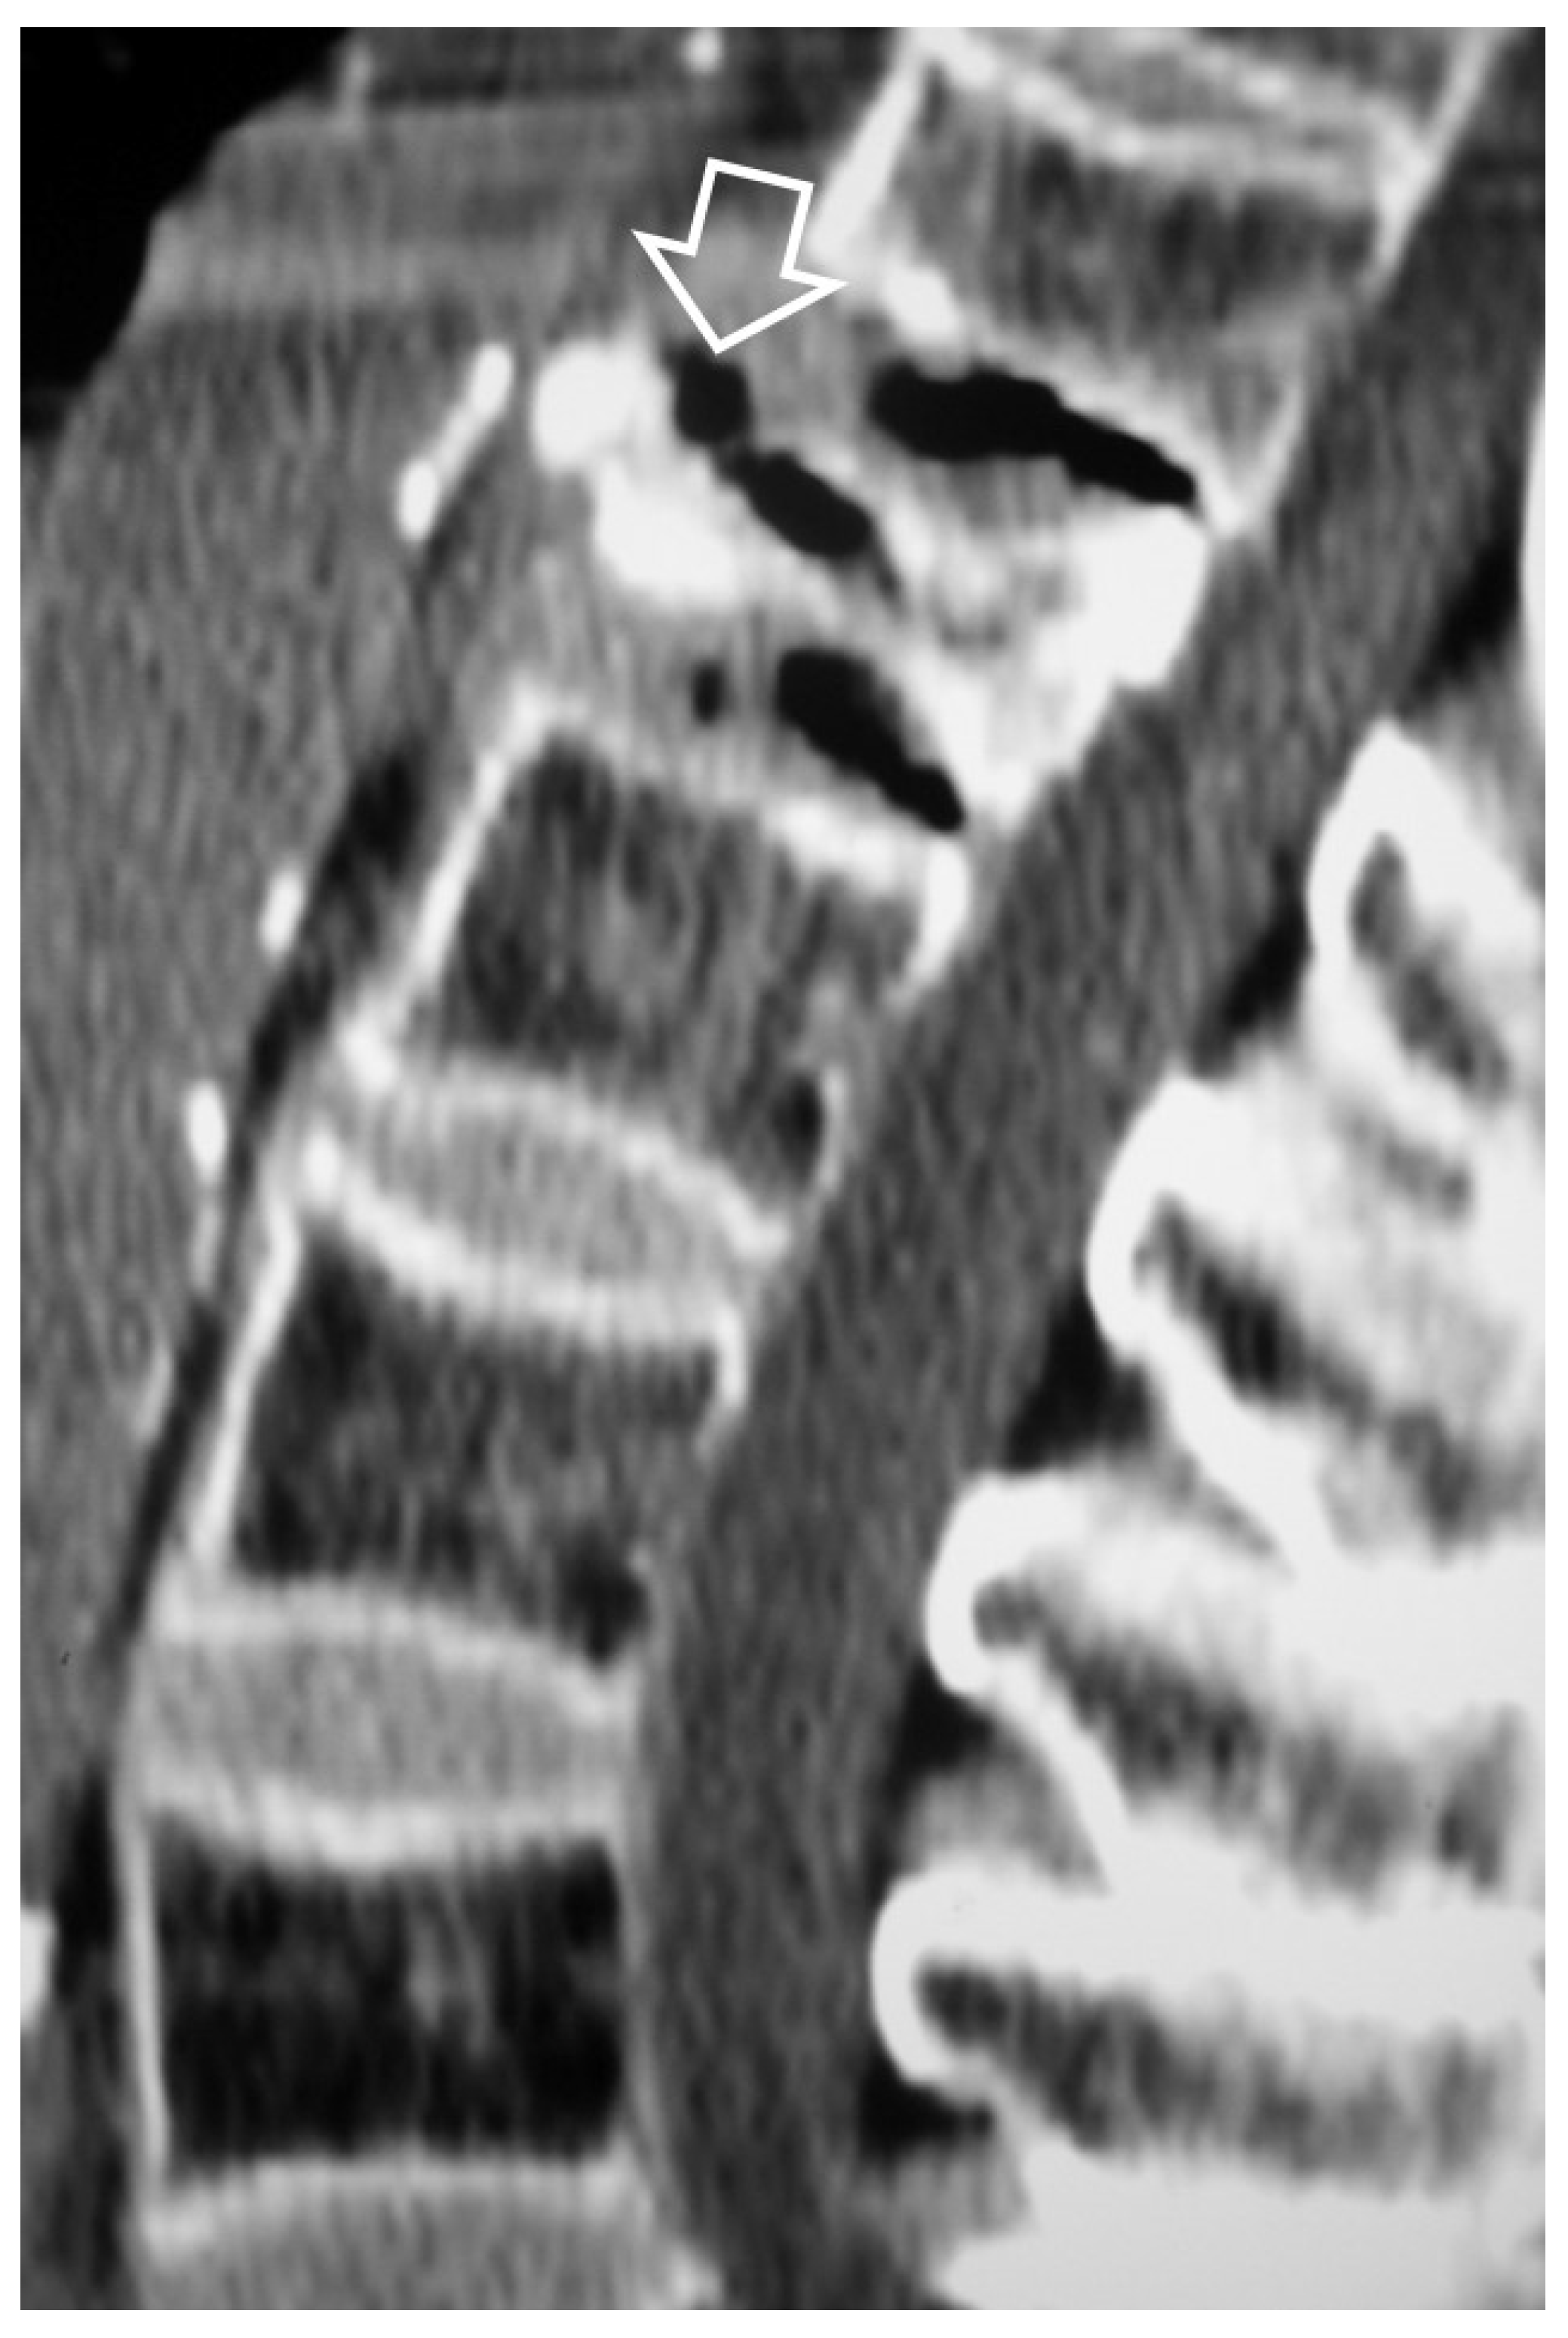

1. a.v. Crystal Deposition

- Ring D, Vaccaro AR, Scuderi G, Pathria MN, Garfin SR Acute calcific retropharyngeal tendinitis. Clinical presentation and pathological characterization. J Bone Joint Surg Am 1994, 76, 1636–1642. [Google Scholar] [CrossRef] [PubMed]

- Offiah CE, Hall E Acute calcific tendinitis of the longus colli muscle: spectrum of CT appearances and anatomical correlation. Br J Radiol 2009, 82, e117–e121. [CrossRef]

- Bouvet JP, le Parc JM, Michalski B, Benlahrache C, Auquier L Acute neck pain due to calcifications surrounding the odontoid process: the crowned dens syndrome. Arthritis Rheum 1985, 28, 1417–1420. [CrossRef] [PubMed]